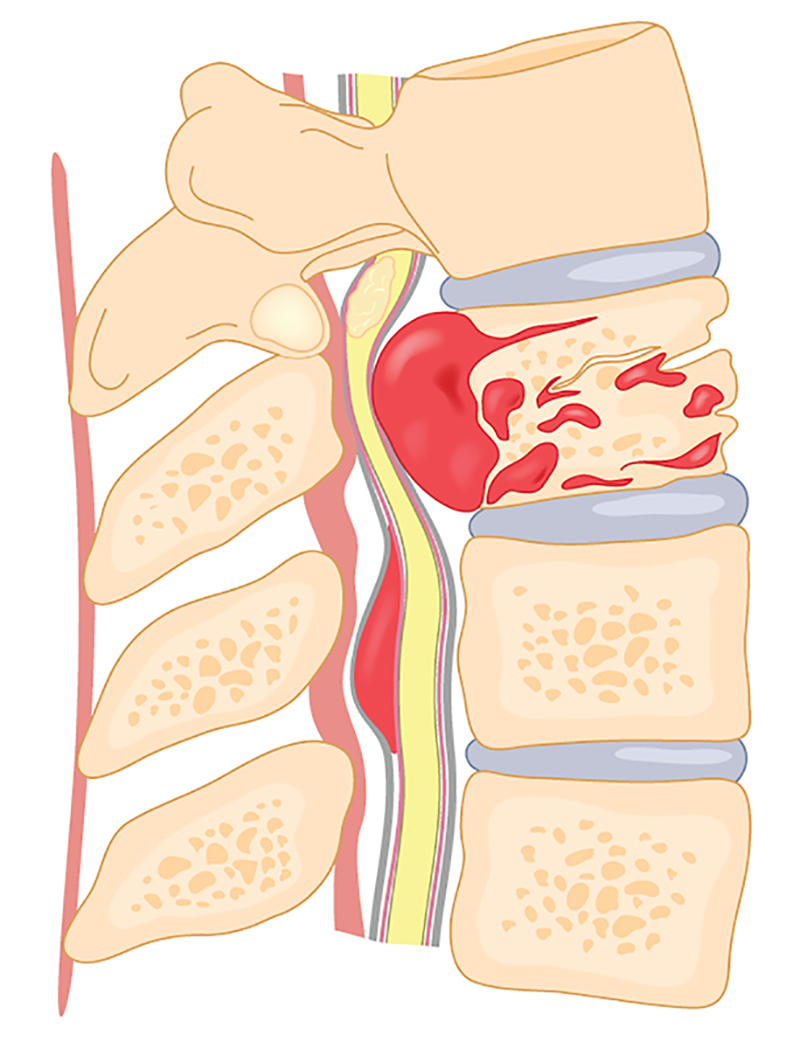

سیاتیک و درد کمر

سیاتیک یکی از شایعترین دلایل انواع کمردرد است که به علت فشار بر عصب سیاتیک ایجاد میشود. این درد معمولاً از کمر شروع شده و به باسن و پاها انتشار مییابد. بیماران اغلب از بیحسی، سوزنسوزن شدن یا ضعف پاها شکایت دارند.

فیزیوتراپیستها با تمرینات اصلاحی، کشش عضلات و استفاده از دستگاههای تخصصی، به کاهش فشار روی عصب سیاتیک کمک میکنند. درمان سریع این مشکل از بروز عوارض جدیتر جلوگیری خواهد کرد. در موارد شدید، ممکن است جراحی لازم باشد.